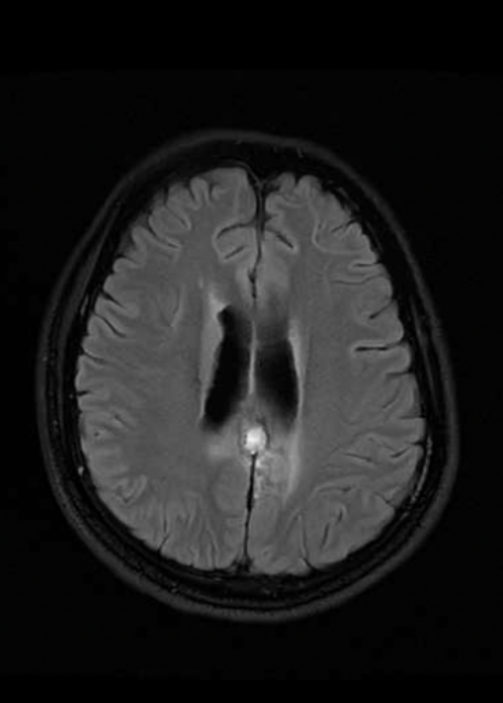

在康复医学科执行主任樊永梅指导下,科室主治医师李慧立即为患者进一步进行腹部脏器和脑部检查。最终,发现患者头颅磁共振可见虫体移动的隧道征,腹部CT发现肝脏两个团块状病灶,考虑寄生虫感染病灶可能。得到这些线索后,康复医学科邀请桂林市疾控中心及医院神经外科、神经内科、放射科、消化内科、病理科、院感中心驻桂湘雅专家进行多学科大会诊。经过综合分析,专家团队诊断考虑患者为脑寄生虫病。同时脑部病变病理检查结果显示,患者大量急慢性炎症细胞浸润,局灶有微脓肿形成,以淋巴细胞、中性粒细胞为主,散布嗜酸性粒细胞,考虑寄生虫病变可能。